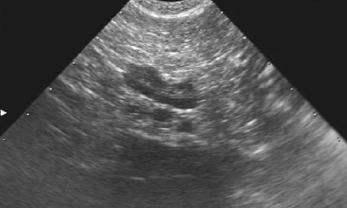

レントゲン検査は、肝臓全体の大きさや形状を見る検査です。超音波検査は、肝臓実質部分をより詳細に検査することができます。血管・胆管の走行や胆嚢の内部構造まで確認できます。しかしながら、超音波で確定診断をできる肝臓疾患は限られています。